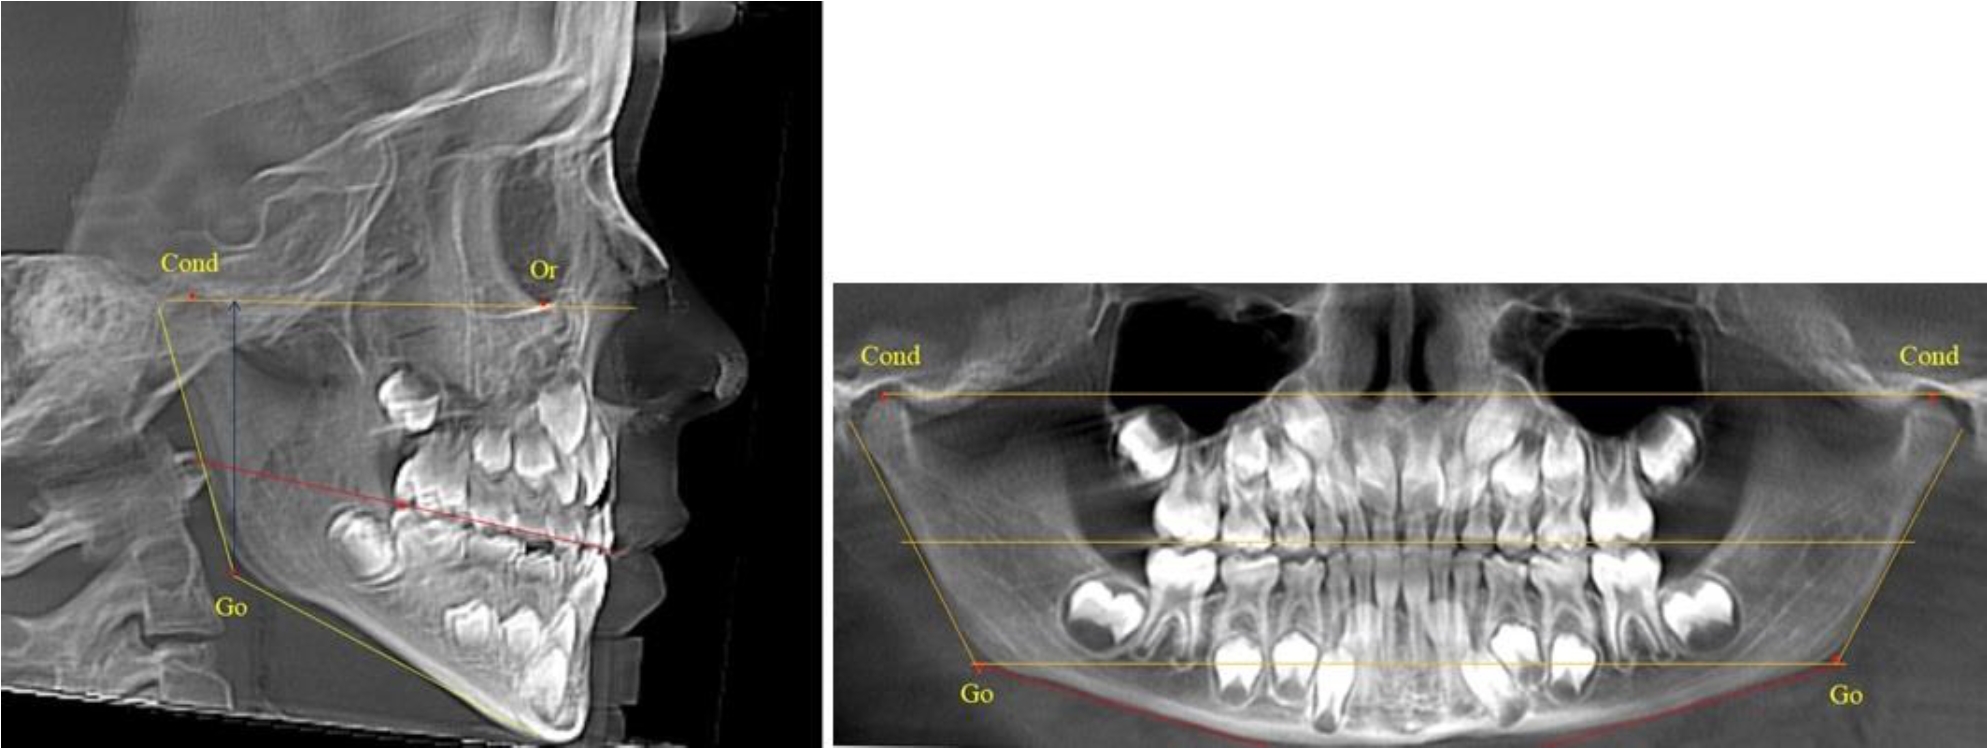

На боковых телерентгенгенограммах вершину суставной головки обозначали точкой кондиион Cond. Касательные линии к ветви и телу нижней челюсти пересекались в точке, которую обозначили Go. Точкой hPOcP обозначали дистальный бугорок нижнего второго моляра вблизи окклюзионного контура коронки. Указанный ориентир соединяли с межрезцовой точкой при построении окклюзионной линии. Высота ветви определялась расстоянием Go-Cond. Окклюзионная линия служила границей между верхней (окклюзионно-суставной) линией и нижней (окклюзионно-альвеолярной) линией.

На ортопантомограмме точки Cond соединяли между собой суставной линией Cond-Cond. Касательная к ветви нижней челюсти соединяла выступающие точки, которые соединялись в области угла и определяли положение точки гонион Go с обеих сторон, которые соединяли гониональной линией Go-Go.

Горизонтальная линя, соединяющая окклюзионные точки hPOcP, определялась как окклюзионная горизонталь.

Во 2-й группе были проанализированы 11 телерентгенограмм и 11 ортопантомограмм, что составило (10,38 ± 2,96) % от числа изученных рентгенограмм. На всех рентгенограммах первые постоянные моляры были установлены в окклюзии, и произошла смена нижних медиальных резцов.

На всех парах рентгенограмм угол нижней челюсти, измеренный на телерентгенограмме, так же, как и в 1-й группе, соответствовал углу, полученному при построении угла на ортопантомограмме. Окклюзионная линия делила ветвь на два отдела (рис. 2).

Рис. 2. ТРГ и ОПТГ пациента после прорезывания первых постоянных моляров

Как на ортопантомограмме, так и на телерентгенограмме высота ветви у детей 2-й группы составляла (46,54 ± 2,87) мм, что было несколько больше, чем у детей 1-й группы (р ˂ 0,05). При этом высота верхней окклюзионно-суставной части была (25,42 ± 1,59) мм, а нижней – (21,12 ± 1,77) мм.

Таким образом, верхняя часть была несколько больше нижней, что и определяло рост обеих частей ветви.

Относительные показатели соразмерности частей ветви нижней челюсти показали, что отношение высоты верхней части ветви к нижней в среднем составляло 1,21 ± 0,12. Отношение общей высоты ветви к верхней ее части составляло 1,83 ± 0,13, а отношение общей высоты ветви к нижней ее части было 2,20 ± 0,16, и достоверных различий по относительному показателю отношения всей высоты к верхней и нижней челюсти нами не отмечено (р ˃ 0,05).